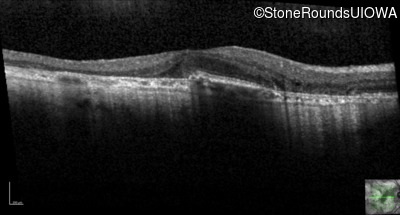

Age at visit: 51 years

This 51 year old woman first experienced some abnormality in her distance vision when she was 27 years old. She feels that her vision has been stable since that time.